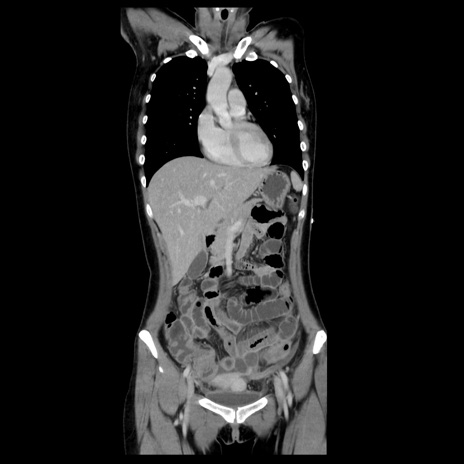

【症例】40歳代女性

【主訴】上下腹部痛

【現病歴】2日目から下腹部痛あり。夜間は痛みで眠れなかった。昨日より上腹部痛と下痢が出現。臥位で痛みは軽快したため、休んでいた。本日になって臥位でも立位でも痛みが強くなってきたため救急要請。

【既往歴】子宮内膜症

【身体所見】部:平坦・軟、左上下腹部に圧痛あり、反跳痛あり。

【データ】WBC 21800、CRP 26.78

CT